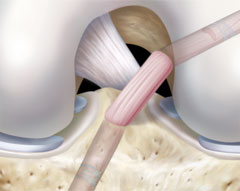

The Centre is headed by Dr Bibek Kumar Rai MBBS. DNB (Ortho), D.Ortho, Mch (Ortho), FIMS, MNAMS. Ph.D, Consultant Orthopaedic Surgeon (Joints Replacement & Arthoscopy) who is an eminent figure with over 10 years of Experience in the field of Joint Replacement Surgery & Arthroscopic Surgery ( KEY HOLE SURGERY ) of the Knee & the Shoulder nationally & internationally. He has worked abroad for several years in the field of Joints Replacement Surgery , Sports Medicine & Arthroscopic Surgery.

B K R Advance Orthopaedics Center is one of the Best Centres in the Bihar offering facilities of Minimally Invasive Orthopaedic Surgery dealing with Joint Replacement Surgery , Joint Surgery , Arthroscopic Surgery.

B K R Advance Orthopaedics Center is one of the Best Centres in the Bihar offering facilities of Minimally Invasive Orthopaedic Surgery dealing with Joint Replacement Surgery , Joint Surgery , Arthroscopic Surgery.

B K R Advance Orthopaedics Center is one of the Best Centres in the Bihar offering facilities of Minimally Invasive Orthopaedic Surgery dealing with Joint Replacement Surgery , Joint Surgery , Arthroscopic Surgery.

B K R Advance Orthopaedics Center is one of the Best Centres in the Bihar offering facilities of Minimally Invasive Orthopaedic Surgery dealing with Joint Replacement Surgery , Joint Surgery , Arthroscopic Surgery.